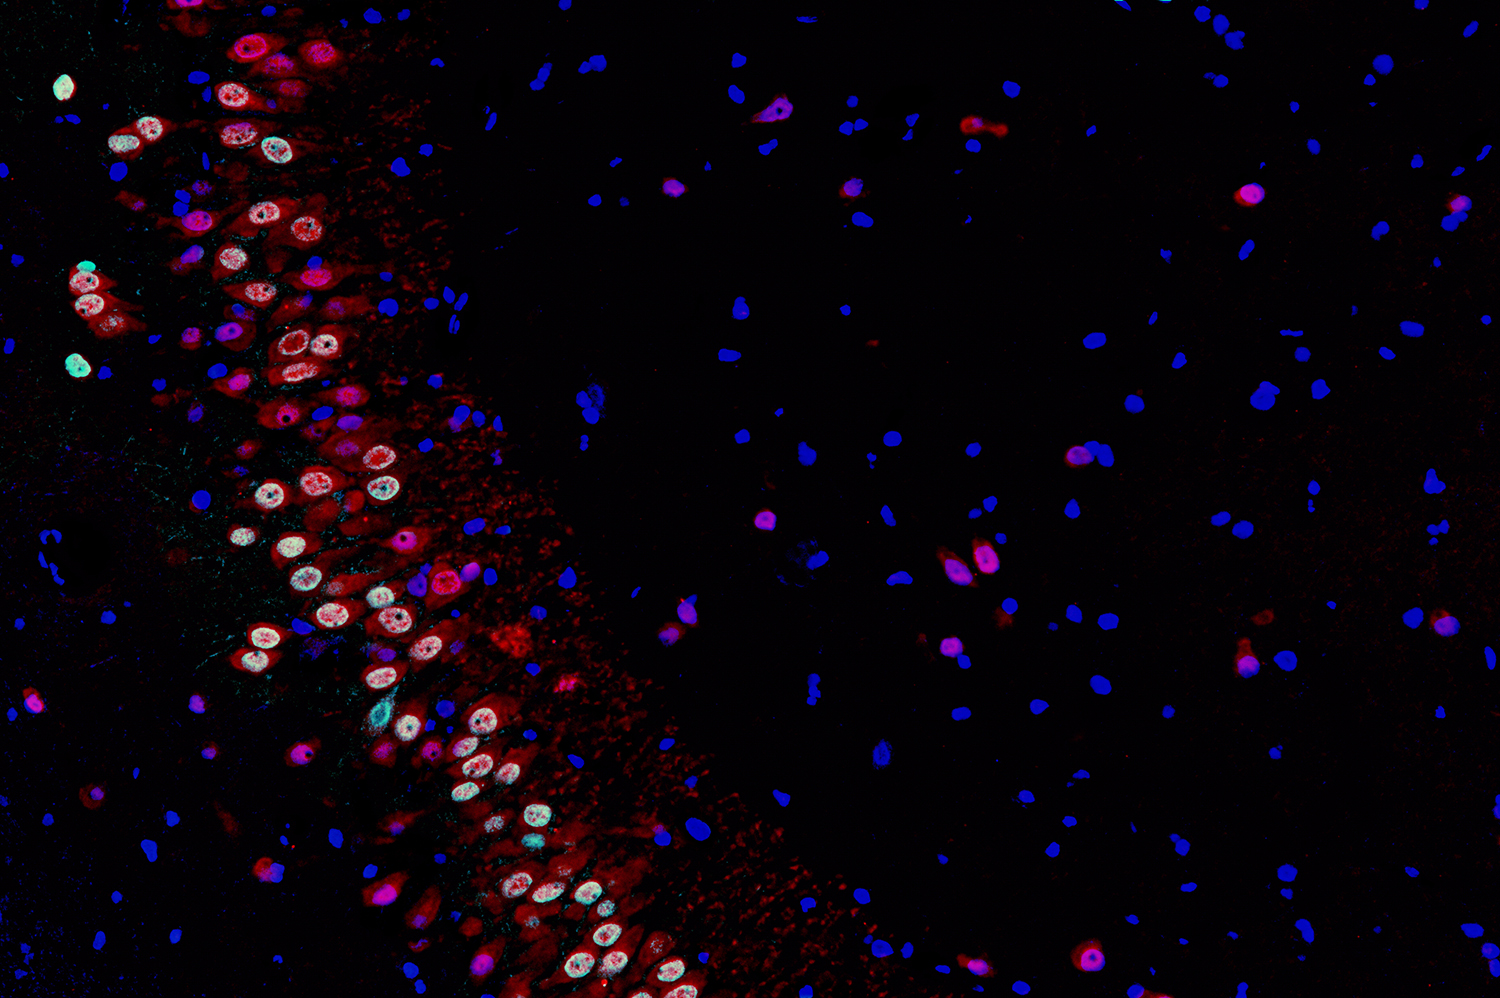

免疫荧光技术是根据抗原抗体反应的原理,先将已知的抗原或抗体标记上荧光素,制成荧光抗体,再用这种荧光抗体(或抗原)作为探针检测组织或细胞内的相应抗原(或抗体)。在组织或细胞内形成的抗原抗体复合物上含有标记的荧光素,利用荧光显微镜观察标本,荧光素受外来激发光的照射而发生明亮的荧光(黄绿色或橘红色),可以看见荧光所在的组织细胞,从而确定抗原或抗体的性质、定位,以及利用定量技术测定含量。

免疫荧光有直接法和间接法两种。(1)直接法:将标记的特异性荧光抗体,直接加在抗原标本上,经一定的温度和时间的染色,用水洗去未参加反应的多余荧光抗体,室温下干燥后封片、镜检。(2)间接法:如检查未知抗原,先用已知未标记的特异抗体(一抗)与抗原标本进行反应,用水洗去未反应的抗体,再用标记的抗抗体(第二抗体)与抗原标本反应,使之形成抗原—抗体—抗体复合物,再用水洗去未反应的标记抗体,干燥、封片后镜检。如果检查未知抗体,则表明抗原标本是已知的,待检血清为一抗,其它步骤的抗原检查相同。标记的抗抗体是抗球蛋白抗体,同于血清球蛋白有种的特异性。